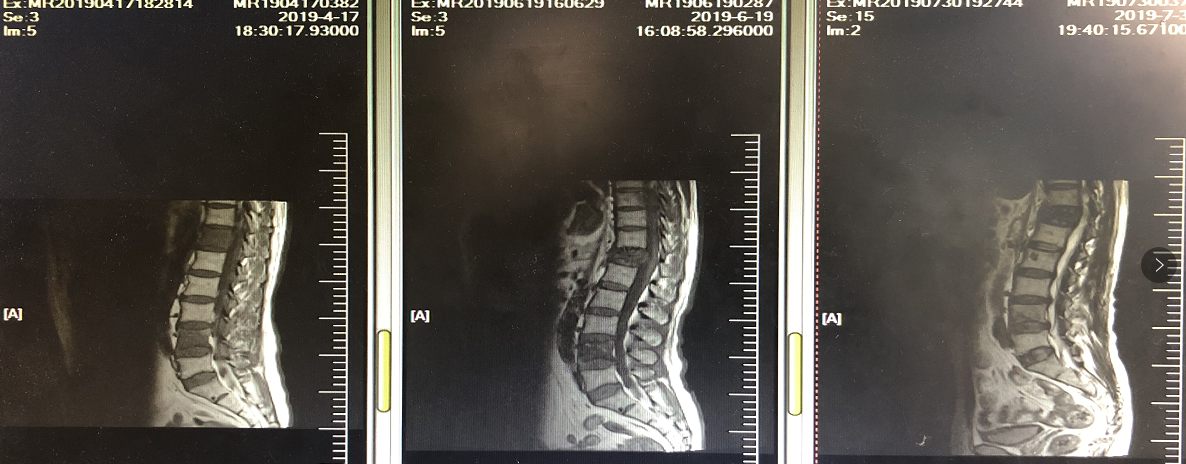

三线治疗前行基因检测,未观察到有意义的驱动突变,PD-L1高表达,>50%; TMB 高,为27.4Mut/Mb。与患者商量后,患者选择信迪利单抗。2019年5~6月接受三线信迪利单抗治疗,方案为信迪利单抗200mg,q21d x 3周期,同时接受唑来膦酸抗骨转移治疗。信迪利单抗治疗3周期后,咳嗽咳血基本消失,仍有腰部疼痛但较前减轻。对治疗耐受良好。复查胸腹部CT:肺部病灶明显缩小,右肾上腺病灶缩小,腰椎病灶变化缓解。目前,患者已经接受信迪利单抗注射液200mg单药治疗第八个周期,体能状态良好,病情改善明显。

图7. 信迪利单抗治疗3周期后肺部病灶明显缩小

图9. 信迪利单抗治疗3周期后腰椎骨转移缓解